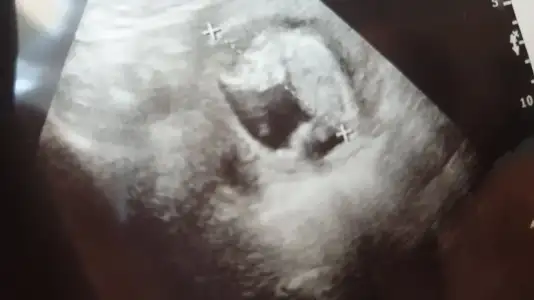

Bunlar bu günden en son da belli etmemişti yine belli etmemiş mi bakalım:)

Eklentiler

• 20200317_145448.webp

20200317_145448.webp

14,3 KB · Görüntüleme: 37